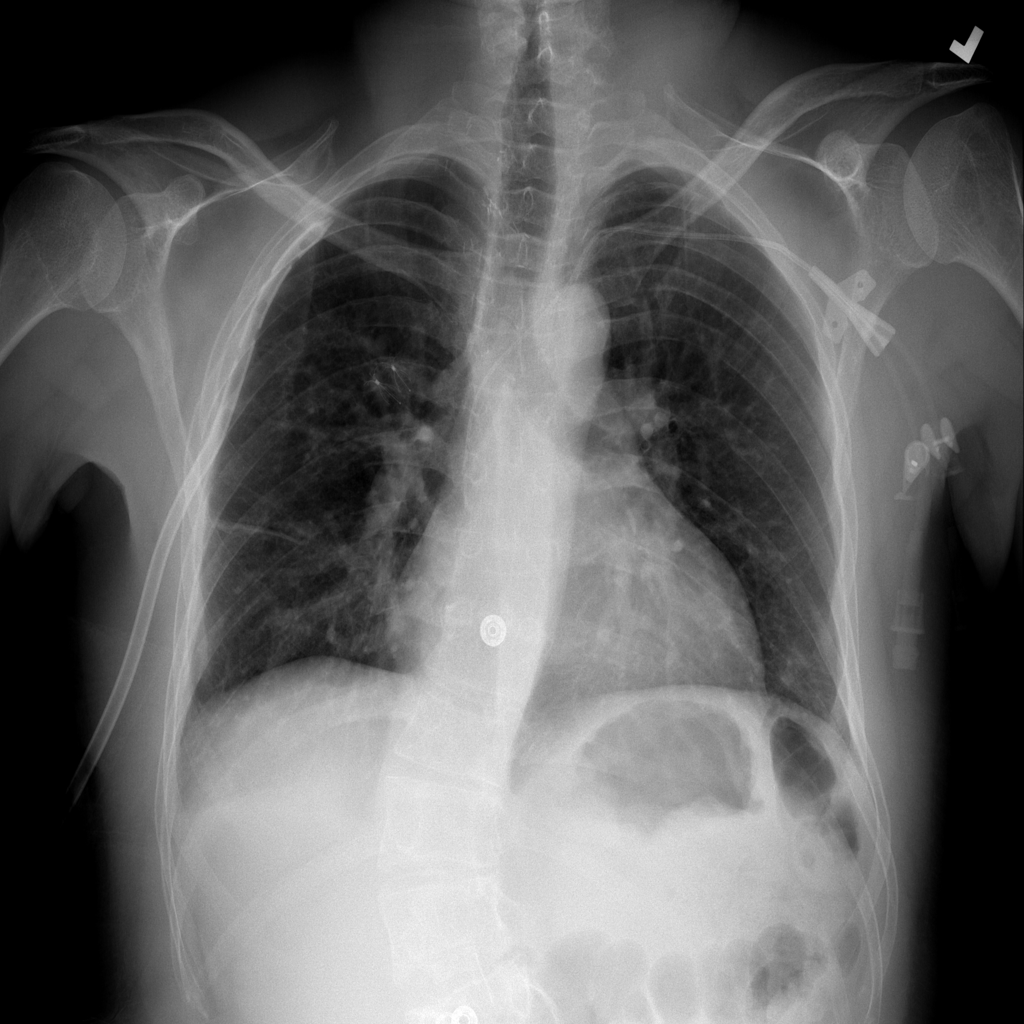

PAT-DB80 · IMG-000Atelectasis

PAT-DB80 · IMG-000

PA